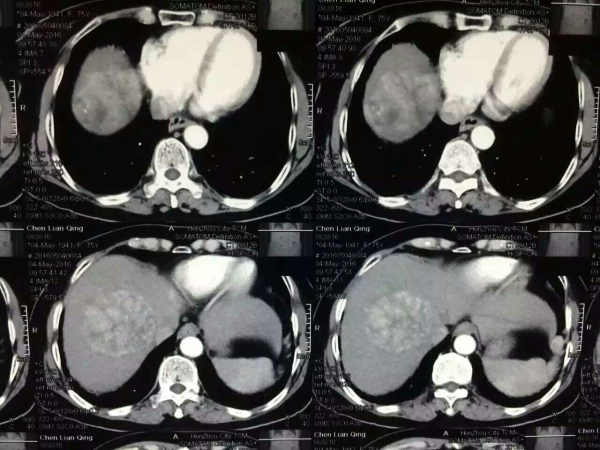

陈阿姨今年76岁,大约1月前老人在体检中被发现有肝占位,考虑肝癌。 她曾在多家医院咨询,因为高龄,手术风险非常大,所咨询的多家医院都不愿意为其实施手术。后来,其家人拿着老人体检的片子找到我院肝胆外科韦杨年主任,韦主任在询问老人病情过程中了解到老人体质不错,遂建议让老人住院检查,待检查结果出来后再决定是否手术。

2016年05月12日,陈阿姨被送进了手术室。手术很成功,切下的肝脏肿瘤有8*7*6公分大小,位于肝右叶。患者术后恢复良好,没有出现肝腹水,蛋白等指标均正常,在肝胆外科护士的精心护理下,老人也未出现肺炎、下肢静脉血栓等任何并发症,术后1周便开心出院。

陈阿姨肝脏术前CT